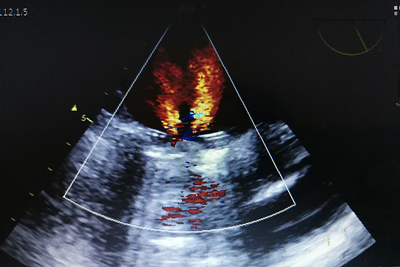

患者邹女士,风湿性心脏病二尖瓣置换术后13年,前几天经胸超声心动图提示二尖瓣机械瓣少量反流,怀疑是否有人工二尖瓣机械瓣瓣周漏。6月14日一早,在市四医院超声医学科彩超室,医务人员为其行局麻下经食道超声心动图检查,清晰显示反流束来自于瓣环内,明确了没有瓣周漏,给临床诊断提供了很好的依据。

经食道超声心动图(TEE)有局部麻醉和全身麻醉两种方式,该技术是将食道探头置于食道或胃底,从心脏后方向前扫查心脏。不仅克服了经胸超声图像受肺气肿、肥胖、胸廓畸形等因素影响的局限性,而且由于食道探头紧邻左心房,能清晰显示心脏后部结构的细微结构,较经胸超声心动图(TTE)明显提高对某些心脏疾患诊断的敏感性和特异性。